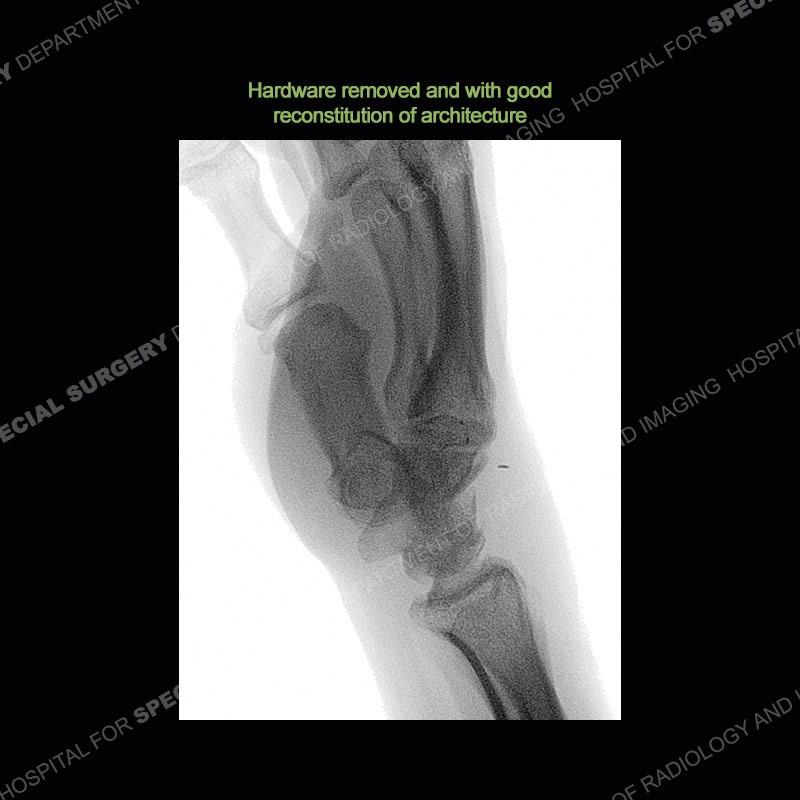

The treatment as the underlying cause of Kienbock’s remains somewhat elusive. Prior to collapse, osteotomies to decrease load or shearing forces to the lunate may be helpful. Once collapse and arthritis have been engendered, fusion and carpectomy have been performed. Now, the role for vascularized bone grafting is being investigated with long term results still being somewhat lacking. Given the young age of the second patient and lack of adjacent, advanced cartilage wear, a vascularized bone graft was performed. The area of necrotic bone was excised, a vascularized bone graft from the distal femur was harvested, and then using microsurgical technique it was grafted to the lunate. A temporary fixation was performed and once the graft was incorporated, the fixation hardware was removed. Although still early in the postoperative period, the patient is doing well.